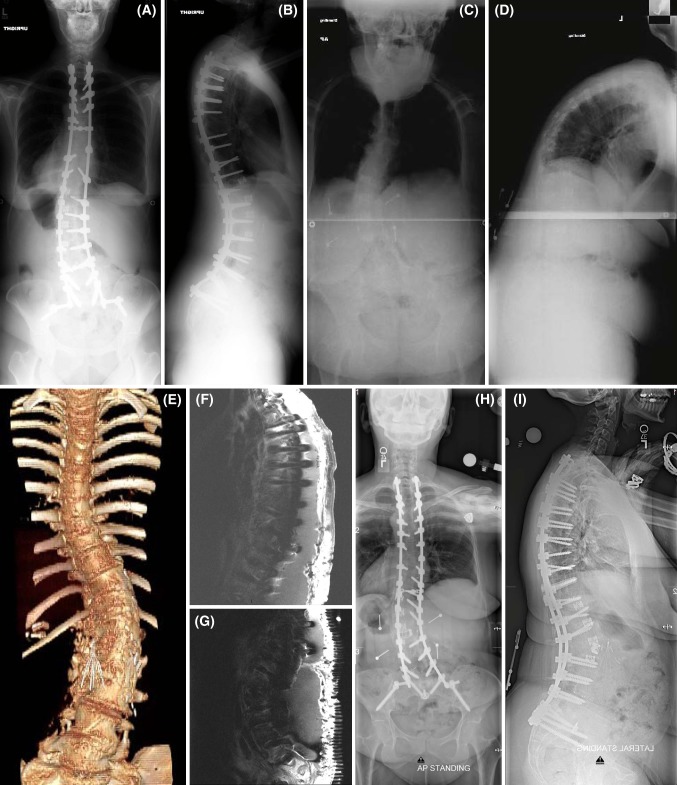

Fig. 1.

Case example of a patient surgically treated for adult deformity who had a major peri-operative complication. A 49-year-old woman with a history of untreated adolescent idiopathic scoliosis presented to an outside facility with back and leg pain and underwent a two-stage procedure: lateral interbody arthrodesis with mesh cages at T11–12, T12–L1, L2–3, and L3–4; followed by T4 to S1 posterior instrumented arthrodesis (stainless steel implants) with L4–5 and L5–S1 transforaminal interbody fusions (TLIF). Post-operative antero-posterior (AP) and lateral full-length X-rays are shown in a and b. This was complicated by a pulmonary embolism and a significant sacral abscess that ultimately required removal of all instrumentation. She presented to the study participant’s site approximately 1 year later with severe back and leg pain and difficulty walking (wheelchair bound) secondary to significant positive sagittal malalignment (C7 plumbline sagittal vertical axis of 23 cm). AP and lateral full-length X-rays are shown in c and d. Three-dimensionally reconstructed CT of the spine is shown in E. Note the caval filter placed following her first surgery. She underwent a 3-stage procedure: (1) L5–S1 anterior lumbar interbody fusion (2) T2 to S1 instrumentation with iliac screws and T4–T11 Smith-Petersen osteotomies, and (3) L2 pedicle subtraction osteotomy, L1–L2 TLIF, and T2–S1 arthrodesis. Within 2 months of surgery, she developed multi-drug resistant E. coli infection with significant and extensive wound fluid collection (f and g show T1-contrasted magnetic resonance images of the thoracic and lumbar spine). She was treated with multiple wound debridements, intravenous antibiotics, and ultimately a wound VAC. Despite this major peri-operative complication, at last follow-up (1 year from her 3-stage procedure), her wound is completely healed and she is off all pain medication, nearly pain free, and ambulating independently. Antero-posterior (AP) and lateral full-length X-rays from last follow-up are shown in h and i